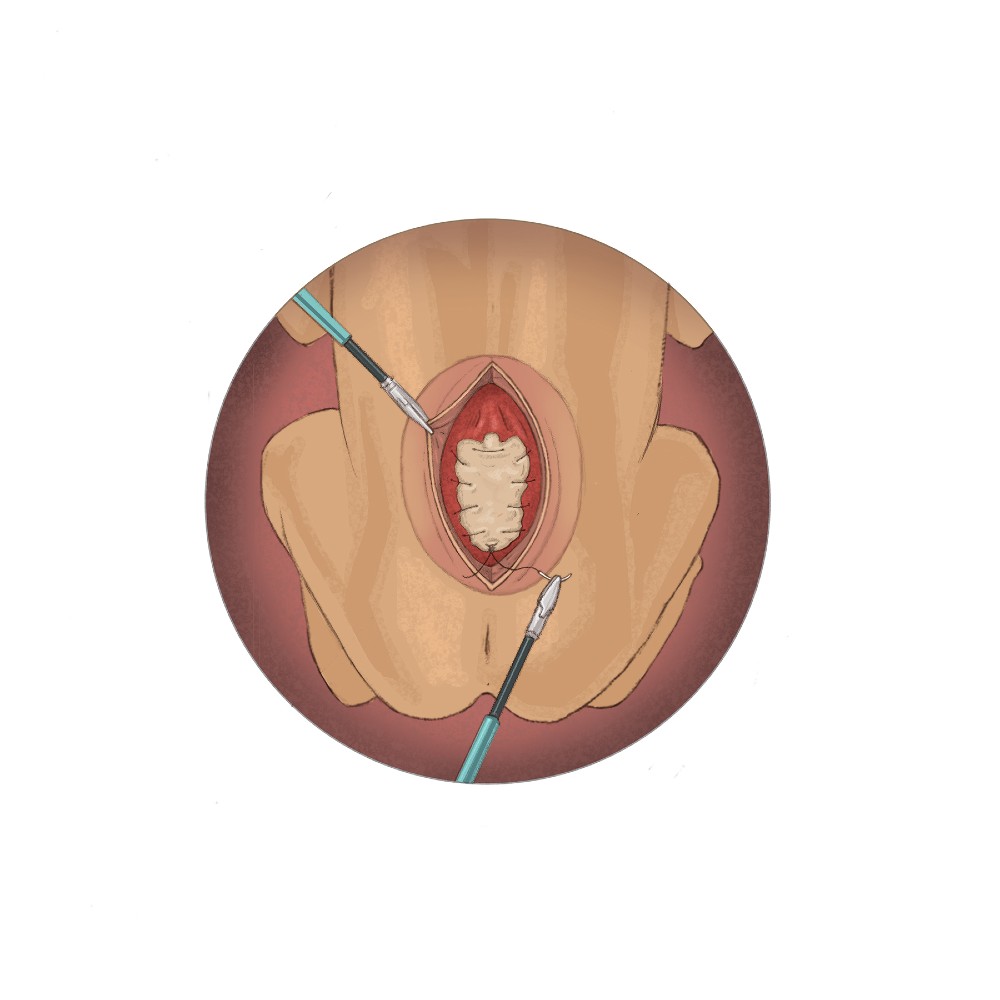

“Our primary outcome measure for the study is successful surgical closure of the spina bifida defect with a watertight patch that approximates native tissue and allows for the natural growth of the spinal cord,” Dr. Papanna says. “The procedure differs from in-utero repair, which requires a large incision on the uterus and delivery by cesarean section. Instead, we will repair the spina bifida defect in two layers through three small incisions in the uterus using fetoscopes and tiny surgical tools. The first layer will be closed using a NEOX®Cord 1K patch as a meningeal patch placed over the spinal cord, followed by a second layer of primary closure of the skin. Mothers will undergo vaginal delivery, unless there is an obstetrical indication for delivery by C-section.”

The NEOX Cord 1K patch is made of cryopreserved umbilical cord and amniotic membrane. Extensive laboratory and clinical research on an ocular wound surface has shown that placental tissues help manage inflammation in wounds, facilitate cell proliferation and create an environment for tissue regeneration. NEOX Cord 1K has demonstrated consistently high closure rates in real-world experiences.